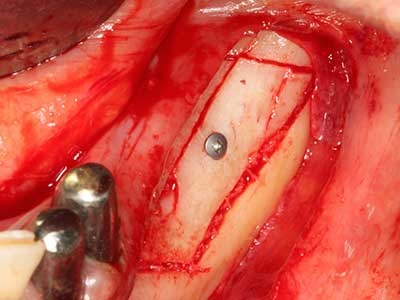

As shown in the past, basically any bone surgery procedure represents a possible indication for piezo surgery. Thus preparation of the mobile segment in distraction osteogenesis (Fig. 23-25) and sandwich osteotomy uses special attachments without endangering the blood supply to the crestal section, which is essential for the success of both techniques (Gonzalez-Garcia, Diniz-Freitas et al. 2008).

Fig. 21: Extended maxillary anterior-tooth defect with indication for distraction osteogenesis with scar tissue after prior operation.

Fig. 22: The mobile segment can be precisely separated with the thin osteotomy saw (W&H Piezomed).

Fig. 23: Final mobilization of the palatally branched distraction segment with the chisel.